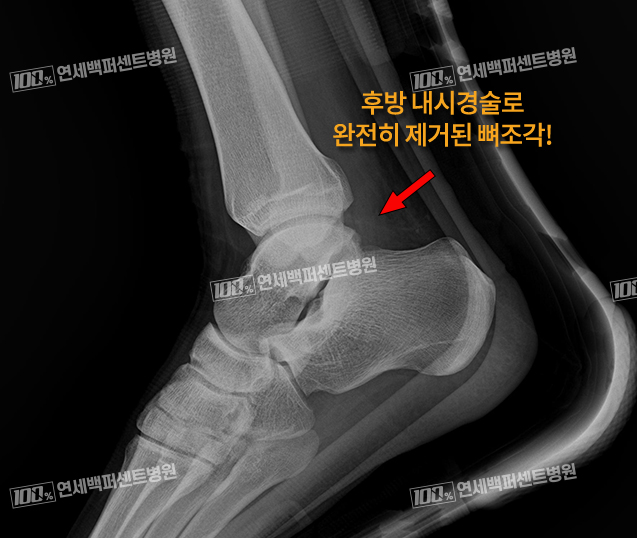

염증, 충돌을 일으키는 뼈조각만 선택적 제거!

발목 후방내시경술 전: X-ray

이OO (22.09.01)

발목 후방내시경술 후: X-ray

이OO (22.10.13)